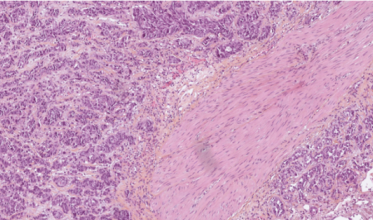

- Le Data Challenge DigiLUT : porté par l’Hôpital Foch, la compétition à été lancée en juin 2024 et avait pour objectif de développer un modèle d’apprentissage automatique capable de prédire la présence de signes de rejet chez un patient greffé pulmonaire. Les compétiteurs ont disposé d’une base de données anonymisées comprenant 2 500 lames d’anatomopathologie numérisées de biopsies pulmonaires de patients greffés. L’objectif final vise à automatiser l'identification des zones pathologiques dans les tissus pulmonaires, un élément clé pour améliorer la reproductibilité des diagnostics et ainsi mieux gérer la prise en charge des patients transplantés.